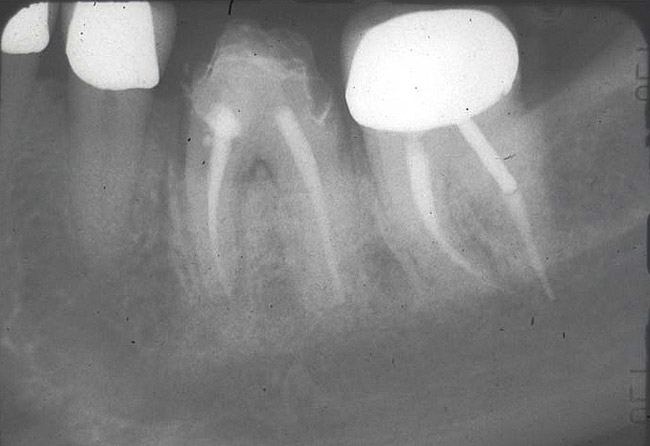

3. Extraction of a hopeless mandibular molar, defect debridement, and placement of an implant in one of the root sockets, followed by restoration with a molar-sized crown. This approach addresses the concern of two implants being placed closely together in the root extraction sockets. However, this treatment appropriately results in a mesial cantilever of the implant restoration and an area of potential plaque accumulation (Figure 1).

Implant placement at the time of mandibular molar extraction should never be attempted if there is any doubt about the ability to place an ideal dimension implant in the appropriate restorative position and attain primary stability. In such a situation it is better to first perform regenerative therapy at the time of tooth removal and place the implant in a subsequent surgical session (Figure 2 through Figure 4).